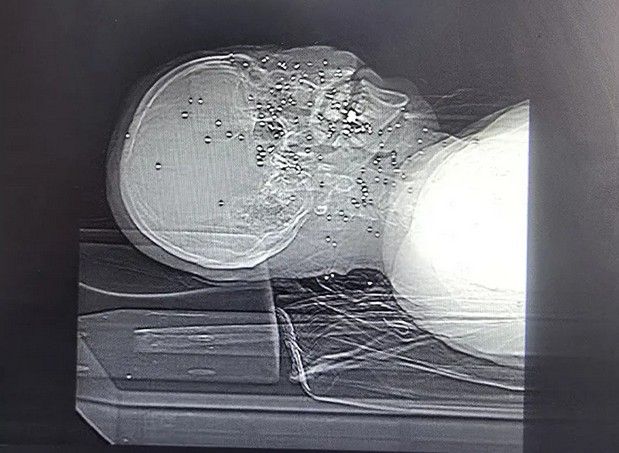

تصاویر رادیوگرافی معترضان نشان میدهد صورت انسانها به هدف تیراندازی تبدیل شدهاند. در چندین پرونده، صورت و سر مجروحان با دهها ساچمه فلزی پر شده است؛ ساچمههایی که در بافت نرم صورت، اطراف چشمها، بینی، فک و حتی نزدیکی جمجمه گیر کردهاند. این الگو با شلیکهای پراکنده و تصادفی همخوانی ندارد و بیشتر شبیه شلیک مستقیم و از فاصله نزدیک به چهره انسانهاست.

در تصویر رادیوگرافی سه تن از معترضان مجروح دیده میشود که در ناحیه سر، صورت و گردن هر کدام حدود ۱۰۰ ساچمه وجود دارد. تعداد ساچمهها در کنار پراکندگی وسیع، اندازه ریز و یکنواخت آنها و نفوذ برخی ساچمهها به جمجمه و بافتهای عمقی صورت، با مشخصات فشنگهای ساچمهریز (Birdshot) تطابق دارد. بر اساس اطلاعات پرونده این بیماران مجروحانی که در عکسهای شماره ۱ و ۲ رادیوگرافی آنها منتشر شده، پس از چند روز جان خود را از دست دادهاند.

«کیانا کثیری»، متخصص پزشک خانواده، که خود نیز در گروههای درمانی در جریان اعتراضات «زن زندگی آزادی» و همچنین اعتراضات دیماه امسال فعالیت داشته، در مورد این سه آسیبدیدگی میگوید: «این سه مجروح مورد اصابت تعداد متعدد ساچمه قرار گرفتند که بدون شک اندام چشم آسیب دیده، این مجروحان دچار التهاب و عفونت در ناحیه بافت گوشتی سر و صورت خواهند شد. از آنجا که در ناحیه صورت تمرکز رگهای خونی و رشتههای عصبی فوق العاده زیاد است، این مجروحان دچار دردهای فوقالعاده شدید خواهند شد که متاسفانه عمل جویدن و بلع را مختل میکند.

در مورد آسیب چشمی باید دید که آسیبدیدگی در چه حد و میزانی است. متاسفانه اگر درمان سریع انجام نشود و چشم عفونت کند مجبور به تخلیه چشم خواهند شد. در هر صورت آسیبدیدگی چشمی حاصل از اصابت ساچمهها باعث ضعف شدید قدرت بینایی خواهند شد.»